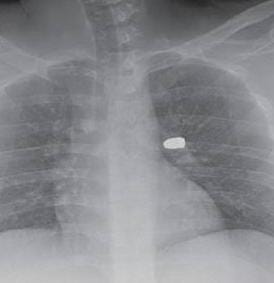

Conforme o boletim de ocorrência, a vítima não soube identificar de onde veio o disparo e correu para a Oficina do Fred, assim que sentiu o impacto. O homem ficou com o tiro alojado no lado esquerdo da costa, mas sem risco de vida conforme relato médico, logo ele foi encaminhado para o hospital.